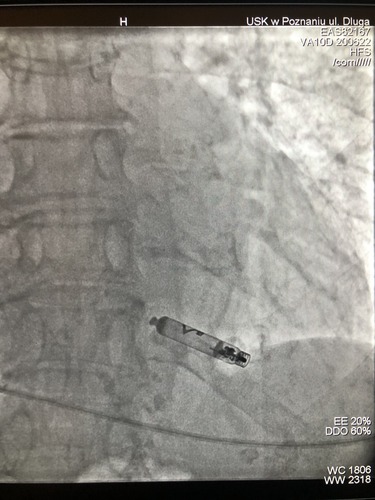

Tak wygląda nowoczesny bezelektrodowy stymulator. Po raz pierwszy w Polsce wszczepili go pacjentce poznańscy kardiolodzy z Uniwersyteckiego Szpitala Klinicznego. Drugi taki sam zabieg w tym samym czasie odbył się w Krakowie.

Zdjęcie ilustracyjne / Fot. Uniwersytecki Szpital Kliniczny w Poznaniu

Pacjentka w Poznaniu dostała pierwszy na świecie dwukomorowy bezelektrodowy stymulator serca. Kapsułki - stymulatory komunikują się ze sobą niskonapięciowymi impulsami w sposób zbliżony do alfabetu Morse’a. Dzięki temu możliwa jest nie tylko stała stymulacja serca, ale także jednoczesna właściwa synchronizacja między pracą prawego przedsionka i prawej komory serca pacjenta.